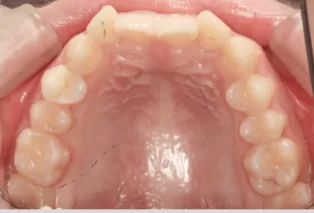

Photos intra-orales après traitement